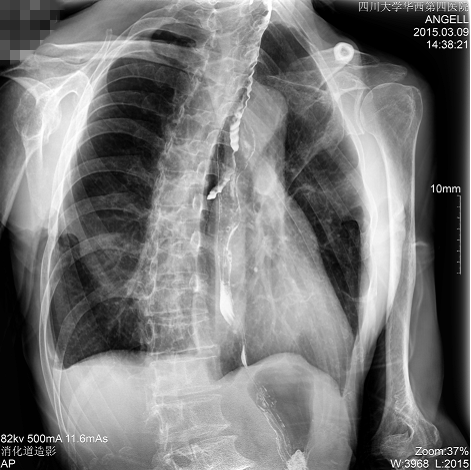

如下圖所示:該患者因吞咽時感到很難受,進(jìn)食時也經(jīng)常咳嗽故就醫(yī)診斷。華西醫(yī)院醫(yī)生使用動態(tài)DR為病人進(jìn)行消化道造影診斷,要求他吞鋇后發(fā)現(xiàn),食道各段通過順利,形態(tài)規(guī)則,雙側(cè)梨狀窩不對稱左側(cè)稍淺,多次吞咽動作后,仍見鋇劑滯留,并見鋇劑進(jìn)入氣管,屬于會厭征陽性。會厭功能紊亂,鋇劑進(jìn)入了氣管。

圖為斜位:通過動態(tài)影像可以清楚看到鋇劑進(jìn)入了支氣管道